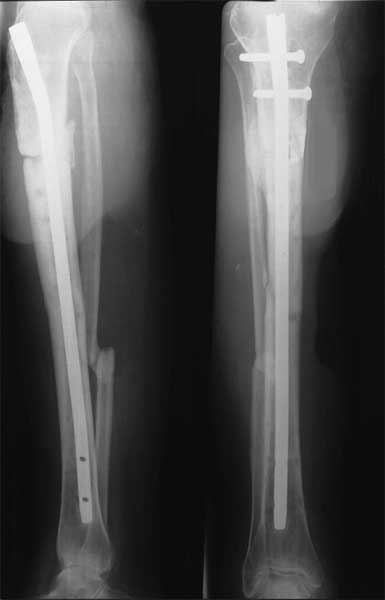

胫骨多段骨折外固定架术后1年,形成骨不连。取除外固定架,

改用髓内钉固定,6个月后骨折愈合。